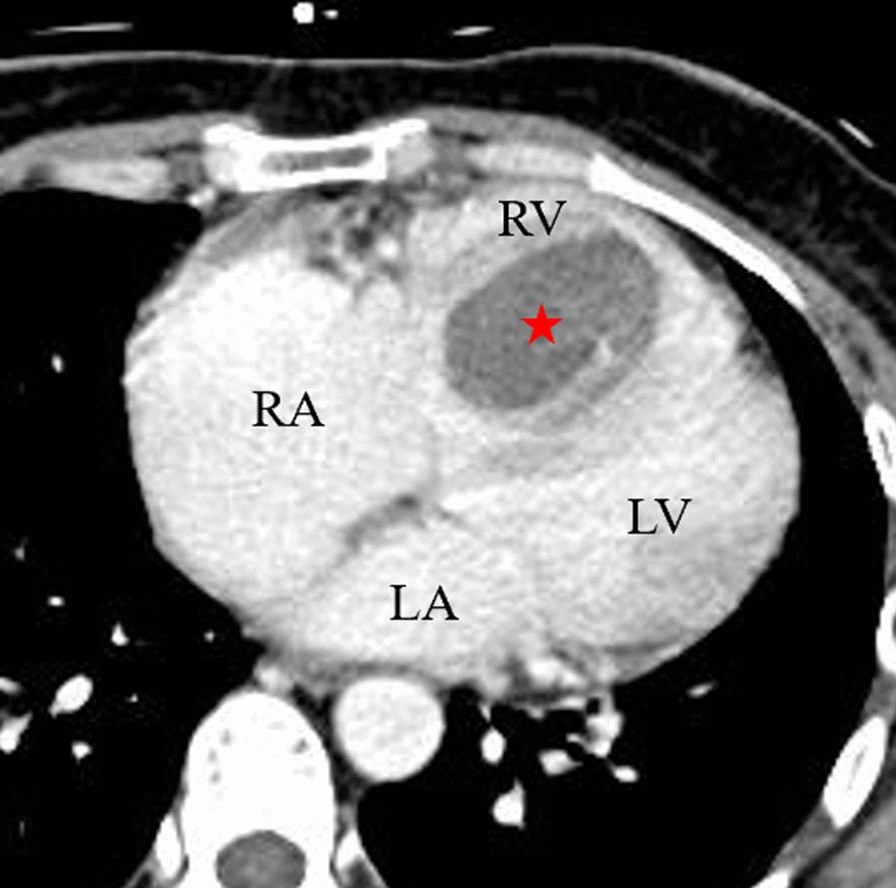

Fig. 2From: Giant right ventricular myxoma presenting as right heart failure with systemic congestion: a rare case reportContrast-enhanced computed tomography showed the tumor in RV had no contrast effect (red star); LA left atria, LV left ventricle, RA right atria, RV right ventricleBack to article page